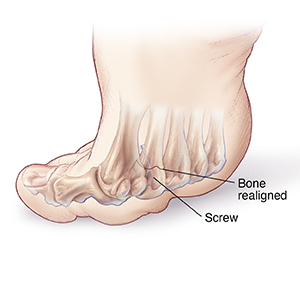

Bone removal

The affected metatarsal bone is cut and aligned with the other metatarsals (oblique osteotomy). Screws or pins may be used to hold the bone in place. Only part of the metatarsal bone is removed. The plantar callus should go away on its own over time.